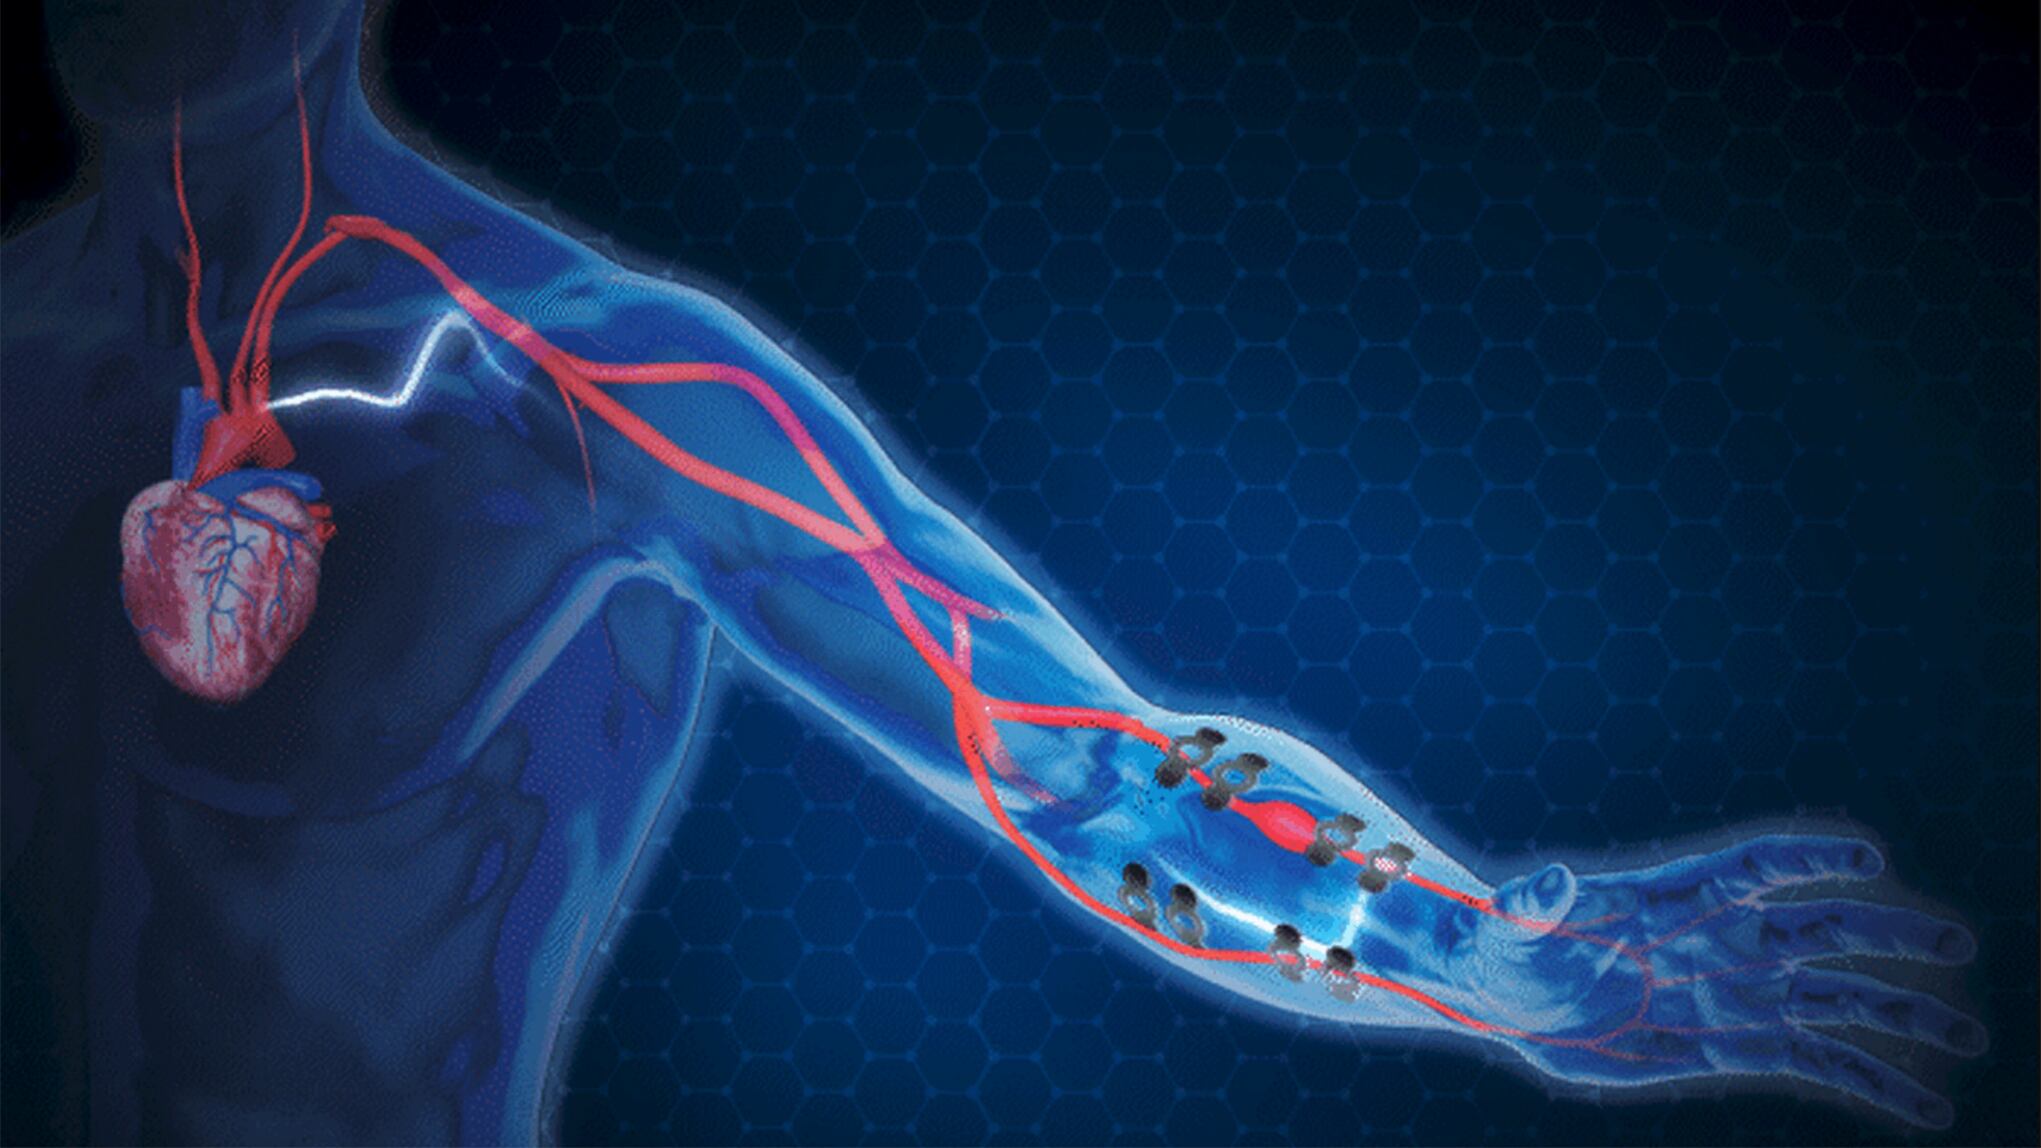

La presión arterial es uno de los indicadores más importantes de la salud del corazón, pero su medición no es muy práctica, ya que los dispositivos basados en brazaletes han sido el estándar de oro durante décadas. Por eso, un grupo de científicos estadounidenses desarrolló tatuajes electrónicos para hacer más eficiente este proceso.

El tatuaje electrónico de los investigadores de la Universidad de Texas en Austin y la Universidad A&M de Texas puede llevarse cómodamente en la muñeca. Proporciona mediciones continuas de la presión arterial con un nivel de precisión que supera a casi todas las opciones disponibles en el mercado.

El llamado E-Tattoo también permite medir la presión arterial en todo tipo de situaciones: en momentos de mucho estrés, mientras se duerme, se hace ejercicio, etc. y no sólo cuando el paciente acude a una cita médica. Está hecho de grafeno, uno de los materiales más resistentes y finos que existen, y puede adaptarse al cuerpo humano.